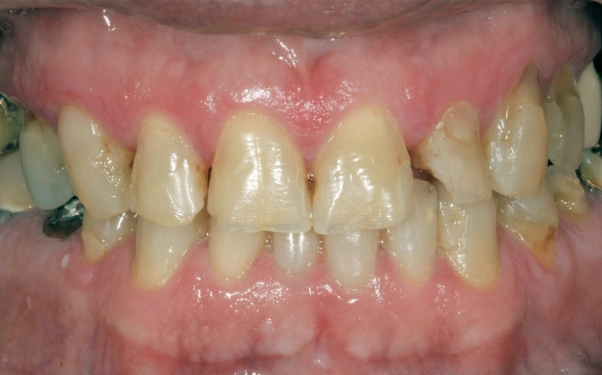

Antes

Quando chegou para a consulta inicial, ele já estava sem o aparelho e apresentava diversos problemas odontológicos, tais como: dentes cariados, quebrados, escurecidos, problemas periodontais e endodônticos (vários dentes com indicação para tratamento e retratamento de canais).

Sua queixa principal era a de que tinha feito um tratamento ortodôntico de mais ou menos dois anos de duração, mas continuava insatisfeito com a função mastigatória e a estética de seus dentes.